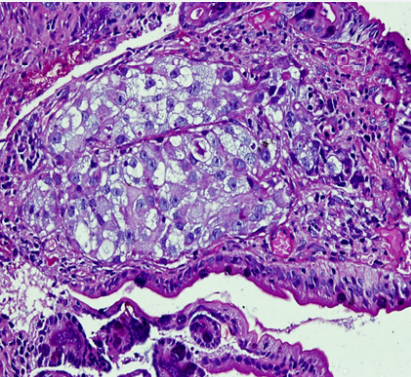

Cancer therapy oncology international journal. Oncology and therapy is an international peer reviewed rapid publication peer review in 2 weeks published 34 weeks from acceptance journal dedicated to the publication of high quality pre clinical clinical all phases observational real world and health outcomes research around the discovery development and use of therapeutics. The goal of this journal is to provide a platform for academicians physicians clinicians and researchers all over the world to promote share and discuss various new issues and developments in all areas of oncology and cancer therapy. Oncology international journal is dedicated to publish the contributions on all aspects of experimental and clinical cancer research.

Oncology international journal is dedicated to publish the contributions on all aspects of experimental and clinical cancer research. The international journal of oncology and cancer therapy is an open access journal. Journal of oncology research and therapy is an international peer reviewed online open access journal publishes high quality articles that are relevant to clinical surgical as well experimental research in the field of oncology.

The journal is concerned with basic translational and clinical research across different disciplines and areas enhancing insight in understanding prevention diagnosis and treatment of cancer. Information about the open access journal international journal of cancer therapy and oncology in doaj. Ctoij is a multidisciplinary open access peer reviewed journal accepts research review articles short communications.